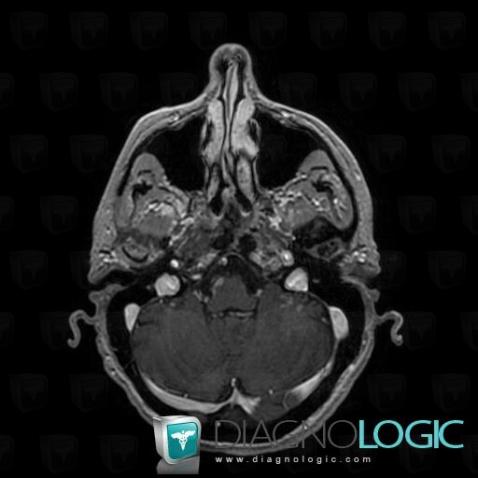

Les images ci-dessous illustrent ce dossier pour les diagnostics Carcinose méningée, Méningite carcinomateuse, pour les modalités (IRM)

Voici les informations spécifiques à l'image clé ci dessus:

- Diagnostic Méningite carcinomateuse, Localisation(s) Région cortico sous corticale, comportant les gammes Lésion sous corticale